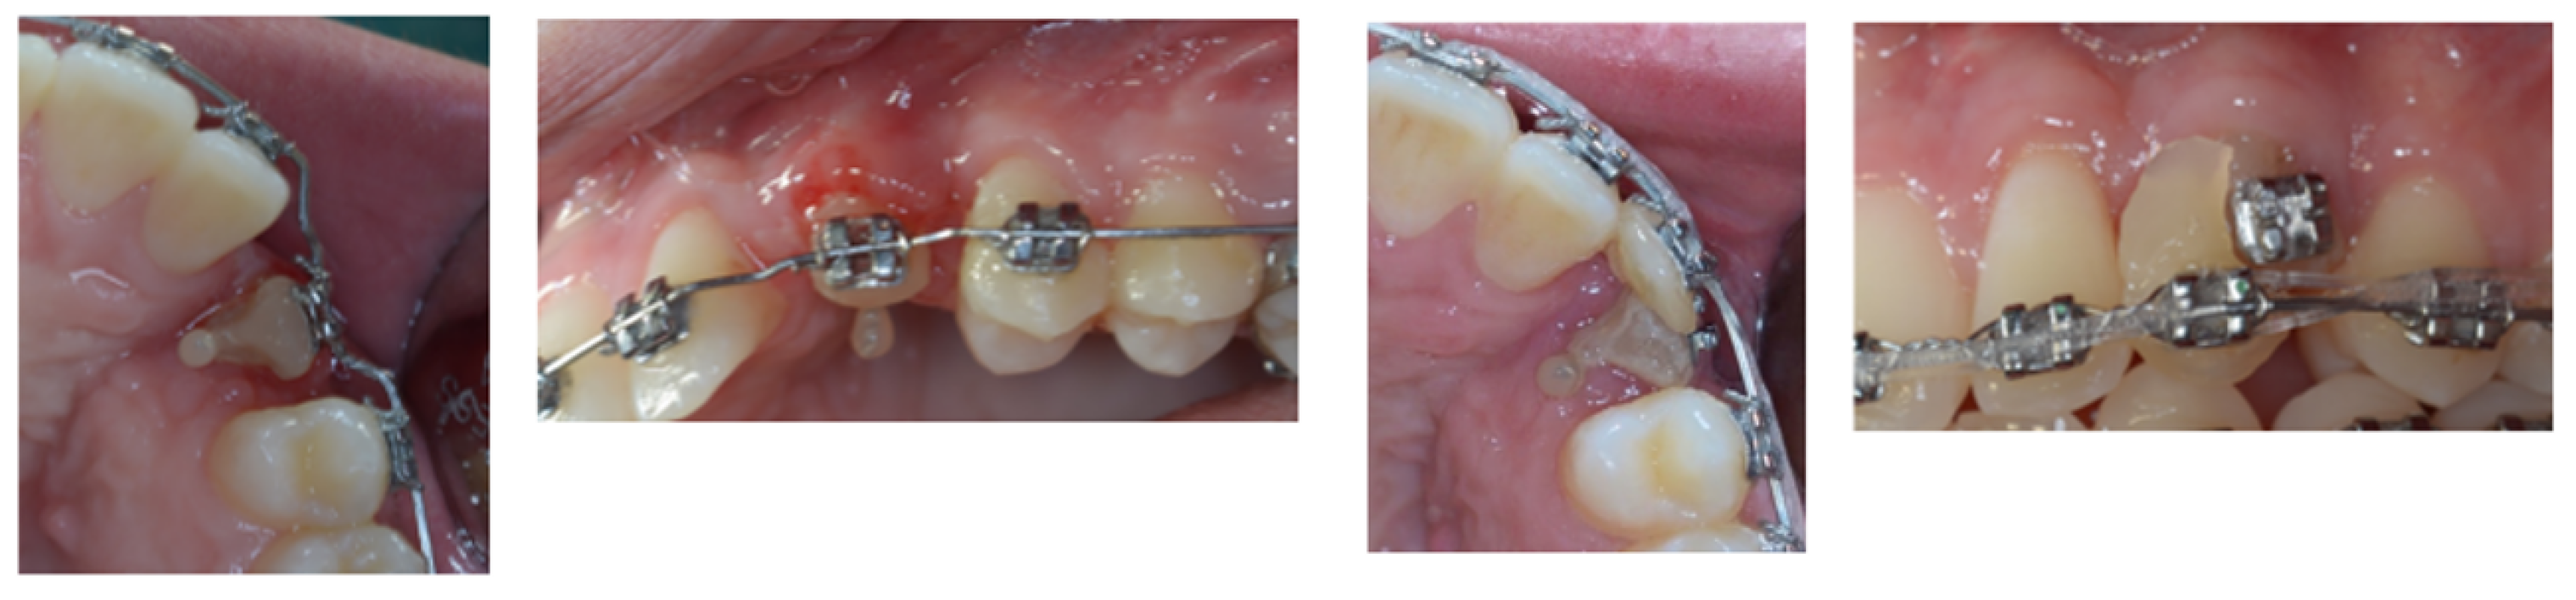

4. Follow-Up and Outcomes